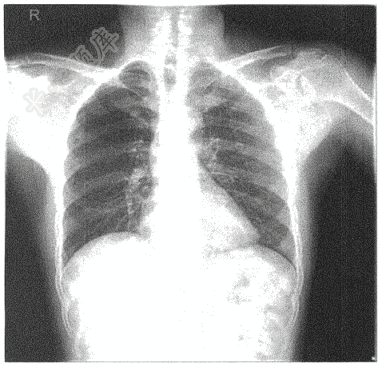

- 单项选择题男,32岁。眼部外伤1天入院。术前检查,胸片如图,诊断为( )

A、两肺无殊

B、心影增大改变

C、左侧肩锁关节半脱位

D、颈部气管狭窄

E、可疑肺结节